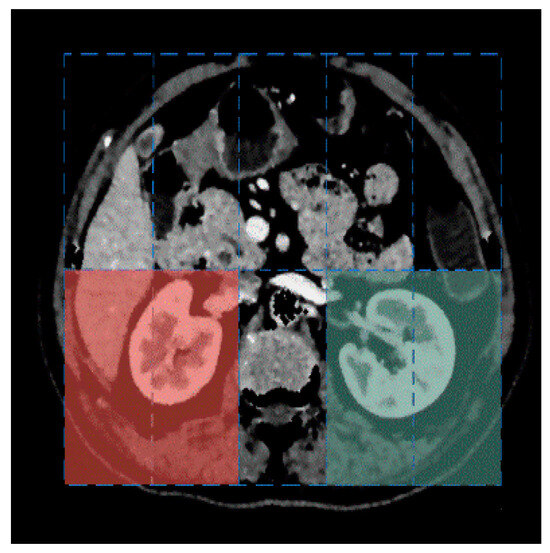

Kidney segmentation from abdominal computed tomography (CT) images is essential for computer-aided kidney diagnosis, pathology detection, and surgical planning. This paper introduces a kidney segmentation method for clinical contrast-enhanced CT images. First, it begins with shape-based preprocessing to remove the spine and ribs. [...] Read more.

Kidney segmentation from abdominal computed tomography (CT) images is essential for computer-aided kidney diagnosis, pathology detection, and surgical planning. This paper introduces a kidney segmentation method for clinical contrast-enhanced CT images. First, it begins with shape-based preprocessing to remove the spine and ribs. Second, a novel clustering algorithm and an initial kidney selection strategy are utilized to locate the initial slices and contours. Finally, an adaptive narrow-band approach based on active contours is developed, followed by a clustering postprocessing to address issues with concave parts. Experimental results demonstrate the high segmentation performance of the proposed method, achieving a Dice Similarity Coefficient of 97.4 ± 1.0% and an Average Symmetric Surface Distance of 0.5 ± 0.2 mm across twenty sequences. Notably, this method eliminates the need for manually setting initial contours and can handle intensity inhomogeneity and varying kidney shapes without extensive training or statistical modeling. Full article